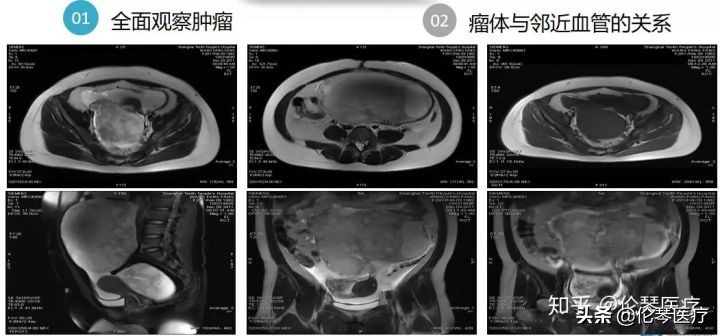

磁共振多参数成像能够对肿瘤里的成分进行分辨,如水份、脂肪、血液、纤维组织等,同时磁共振还有动态增强,便于了解肿瘤血液动力学的变化。磁共振成像范围大(大FOV),一次性能够完成整个腹部的检查,所以很容易了解肿瘤与临近血管的关系。有些病人,肿瘤可能不大,但是已经出现了转移,磁共振能发现临近的骨盆转移、后腹部区转移、骨转移,所以对卵巢肿瘤的诊断价值非常大。

磁共振的另一优势在于多方位成像,成像范围大(大FOV),这也是基于卵巢肿瘤本身具有的特点。因为卵巢肿瘤通常会长很大,占据整个腹部,超声对于这么大的肿瘤,很难了解到细节。而磁共振多方位成像就可以全面了解肿瘤的上下左右关系,以及肿瘤和血管之间的关系。

如图所示病例,初步诊断是常见的卵巢上皮癌,后来通过磁共振的多方位成像,发现肿瘤在腹腔里有几个组成部分,且发现上腹部的胃也有问题。最后,我们术前诊断是胃癌到卵巢的转移,称为库肯勃氏瘤。